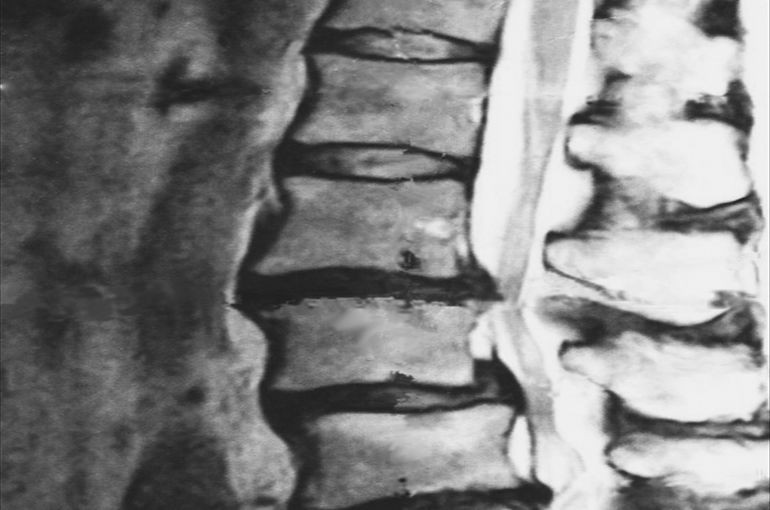

上記写真を使って

簡単に説明します。

そもそも背骨というのは、

1つの骨ではなく、

複数の骨が積みあがって

構成されています。

その1つ1つの骨の間に

クッションの役割をするものが

あります。

これが「椎間板」です。

そして写真には写っておりませんが、

椎間板の中には緩衝材の役割として

「髄核」という部分があります。

『腰椎椎間板ヘルニア』は

何かしらの理由で腰辺りの

背骨付近でこの髄核が椎間板を

つきやぶり後方に出てしまい、

後方にある神経を圧迫して

痛み等の症状が出ている状態です。